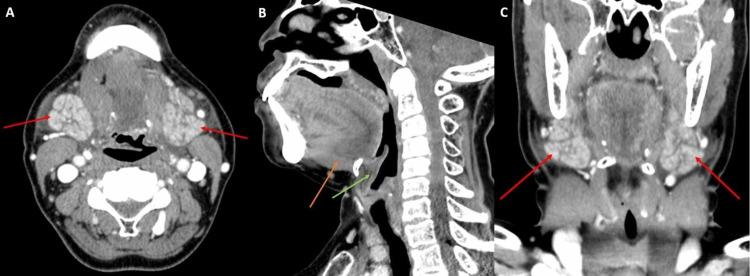

Angiotensin-converting enzyme inhibitors (ACE-i) are commonly used medications to treat hypertension and congestive heart failure. Angioedema is a well-established side effect of ACE-i and most commonly manifests as swelling of the mucosal and extra-mucosal soft tissues in the head and neck. CT with contrast is generally used to evaluate for airway compromise and to exclude other etiologies of edema. Herein we present five cases that illustrate the radiological findings specific to ACE-i-induced angioedema on enhanced CT scans.

血管紧张素转换酶抑制剂(ACE-i)是治疗高血压和充血性心力衰竭的常用药物。血管性水肿是ACE-i公认的副作用,最常见的表现为头颈部黏膜和黏膜外软组织肿胀。增强CT通常用于评估气道是否受阻,并排除其他水肿病因。在此,我们展示5例病例,以说明增强CT扫描中ACE-i诱导的血管性水肿的特异性影像学表现。